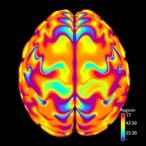

In the continually evolving landscape of neurogenetics, recent research sheds crucial light on the intricate genetic underpinnings involved in Dravet syndrome-like phenotypes. Dravet syndrome, a catastrophic epileptic encephalopathy primarily associated with mutations in the SCN1A gene, has long challenged clinicians and researchers alike due to its severity, early onset, and resistance to traditional anti-epileptic treatments. However, the groundbreaking study authored by A.N. Datta, titled “Beyond SCN1A: genetic diversity in Dravet syndrome-like phenotype and the path to precision treatment,” published in Pediatric Research in 2026, fundamentally advances our understanding by revealing the diverse genetic landscape extending far beyond the well-documented SCN1A mutations.

The canonical view of Dravet syndrome has classically revolved around the SCN1A gene, encoding the alpha subunit of the neuronal voltage-gated sodium channel Na_v1.1. Mutations in SCN1A disrupt sodium channel function, leading to hyperexcitability and the hallmark severe, treatment-refractory epilepsy seen in Dravet patients. However, this narrow focus has obscured the genetic heterogeneity apparent in patients presenting with Dravet-like phenotypes but lacking identifiable SCN1A mutations. Datta’s work delves deeply into these phenotypic overlaps and explores the broader genomic context that influences disease manifestation.

Datta’s investigation also reveals how these genetic differences influence clinical progression, treatment responses, and prognosis. For instance, patients harboring mutations in genes encoding GABAergic signaling components exhibit different seizure profiles and drug responsiveness compared to those with SCN1A mutations. Such genotype-phenotype correlations are crucial for optimizing patient-specific treatment plans and ushering in the era of precision medicine in pediatric epilepsy.